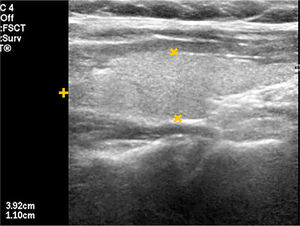

EL TIROIDES NORMAL Y PATOLÓGICOEl tiroides normal al ultrasonido tiene la forma de una letra H (para otros como mariposa), con lóbulos derecho e izquierdo con predominio franco del eje cráneo caudal, algunos más y otros menos estilizados, de contornos lisos, de bordes más bien agudos, generalmente entre 30 y 60mm de eje longitudinal según la literatura (entre 30 y 42mm en mi experiencia) (Figura 1). El istmo también con predominio del eje longitudinal, con un diámetro anteroposterior no mayor a

3mm (Figura 2). La presencia del lóbulo piramidal no es rara, alrededor del 20%11, siendo dependiente la mayoría de las veces del istmo y las otras veces del borde medial del lóbulo izquierdo (Figura 3).